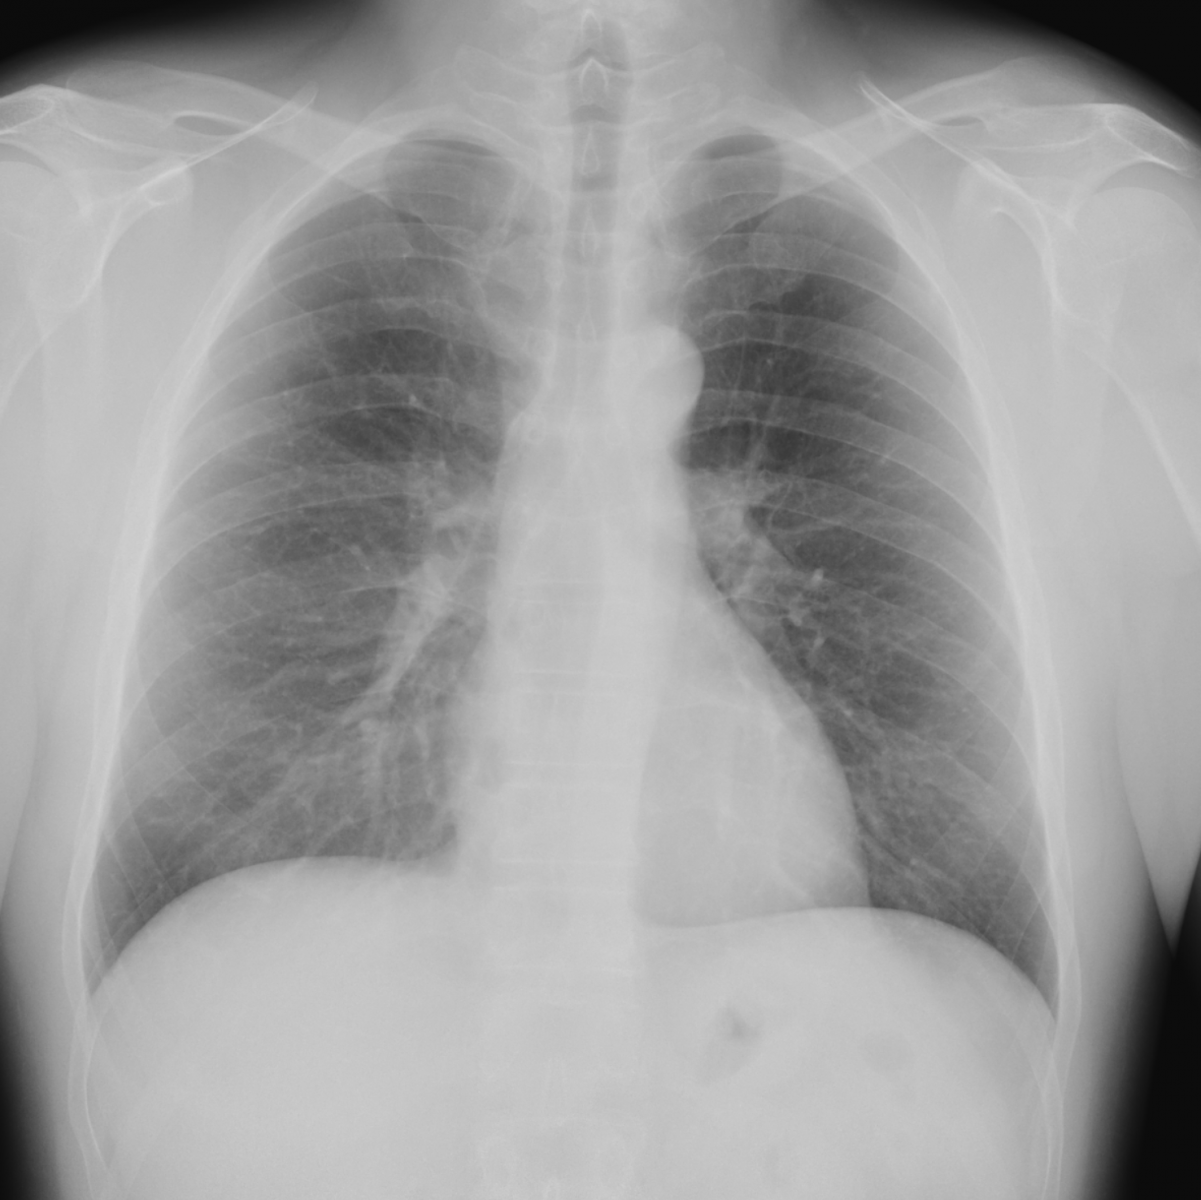

Princip vyšetření je založen na schopnosti rentgenového záření pronikat hmotou a dle vlastností jednotlivých tkání se specificky zeslabovat. Výsledkem je obraz zachycený na citlivý materiál – rentgenový film či detekční systém přístroje. Rentgenové vyšetření se hodí zejména k posouzení kostí a plic. Dále je možné např. z obsahu plynu ve střevech posoudit průchodnost střeva. Na snímcích lze hledat cizí kovová tělesa v těle.

Provádíme kompletní spektrum základních i speciálních skiagrafických vyšetření skeletu i měkkých částí lidského těla.

Ukázky RTG snímků